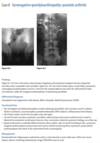

Anteroposterior view of the pelvis

shows diffuse,

uniform, bony sclerosis and a subtrochanteric frac-

ture of the proximal left femur.

A lateral chest ra-

diograph shows the

sandwich appearance of the vertebral bodies caused

by increased sclerosis of the superior and inferior

end plates.

Radiographs of the knees show splaying of the metaphyses and alternating radiolucent bands in the distal

femurs and proximal tibias and fibulas bilaterally. (Erlenmyer flask)

Diagnosis: Osteopetrosis

Defect in osteoclastic resorption.

Precocious (AR Lethal) and Delayed (AD asymptomatic)

Generalized osteosclerosis and diffuse cortical thick-

ening with narrowing of the medullary cavity.